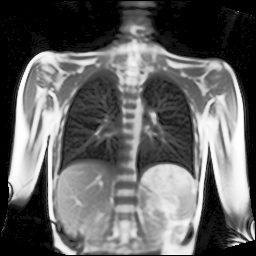

Refer to captionRefer to captionRefer to captionRefer to captionRefer to captionRefer to captionRefer to captionRefer to captionRefer to captionRefer to captionRefer to captionRefer to captionRefer to captionRefer to caption

Figure 5: Maximum inspiration (top row) and maximum expiration (bottom row) for different slice positions of one patient from back to front.

For a complete chest volume coverage, the lung is scanned at different slice positions as shown in Figure 5. At each slice position, a dynamic 2D+t image series with 140 images is acquired. For the further analysis of the image data, all images of one slice position need to be spatially aligned. We choose the image which is closest to the mean respiratory cycle as fixed image of the series. The other images of the series are then registered to this image. Our data set consists of 48 lung acquisitions of 42 different patients. Each lung scan contains between 7 and 14 slices. We used the data of 34 patients for the training set, 4 for the evaluation set, and 4 for the test set.